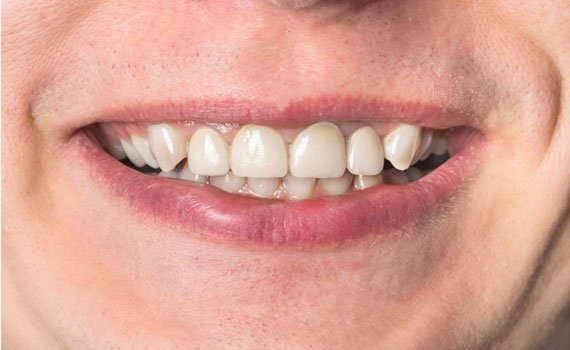

Welcome to Care 32 Dental Clinic & Implant Center, your trusted destination for comprehensive dental care. Located in the heart of the city, we specialize in providing a wide range of dental treatments to ensure the health and beauty of your smile. Our clinic offers advanced technology, a professional team of experts, and a comfortable environment to make your visit stress-free and effective. Whether you're in need of a routine check-up or complex dental procedures, we provide the highest standards of care with personalized attention to meet your needs.